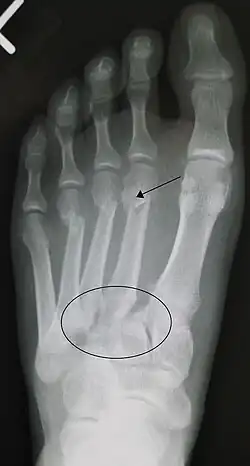

| An X-ray of a Lisfranc injury | |

In a high energy injury to the midfoot, such as a fall from a height or a motor vehicle accident, the diagnosis of a Lisfranc injury should, in theory at least, pose less of a challenge. There will be deformity of the midfoot and X-ray abnormalities should be obvious. Further, the nature of the injury will create heightened clinical suspicion and there may even be disruption of the overlying skin and compromise of the blood supply. Typical X-ray findings would include a gap between the base of the first and second toes.[8] The diagnosis becomes more challenging in the case of low energy incidents, such as might occur with a twisting injury on the racquetball court, or when an American Football lineman is forced back upon a foot that is already in a fully plantar flexed position. Then, there may only be complaint of inability to bear weight and some mild swelling of the forefoot or midfoot. Bruising of the arch has been described as diagnostic in these circumstances but may well be absent.[9] Typically, conventional radiography of the foot is utilized with standard non-weight bearing views, supplemented by weight-bearing views which may demonstrate widening of the interval between the first and second toes, if the initial views fail to show abnormality. Unfortunately, radiographs in such circumstances have a sensitivity of 50% when non-weight bearing and 85% when weight-bearing, meaning that they will appear normal in 15% of cases where a Lisfranc injury actually exists.[10] In the case of apparently normal x-rays, if clinical suspicion remains, advanced imaging such as magnetic resonance imaging (MRI) or computed tomography (CT scan) is a logical next step.[11]